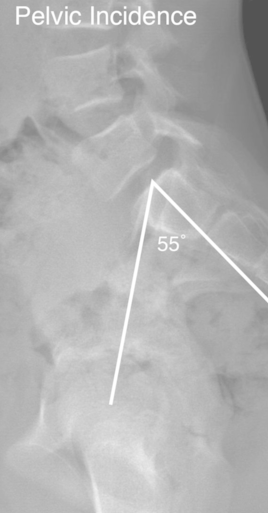

Espondilolisteses

• Qual a definição e as principais características da incidência pélvica (IP)?

A

• Ângulo entre a linha perpendicular ao platô superior do sacro e a linha entre o ponto médio do platô superior do sacro até o centro da cabeça do fêmur

• Normalidade: 50 a 55°

• Principais características:

• Aumentado nos pacientes com listese (escorregamento)

• Parâmetro fixo → anatomia individual

• NÃO prediz a progressão da deformidade